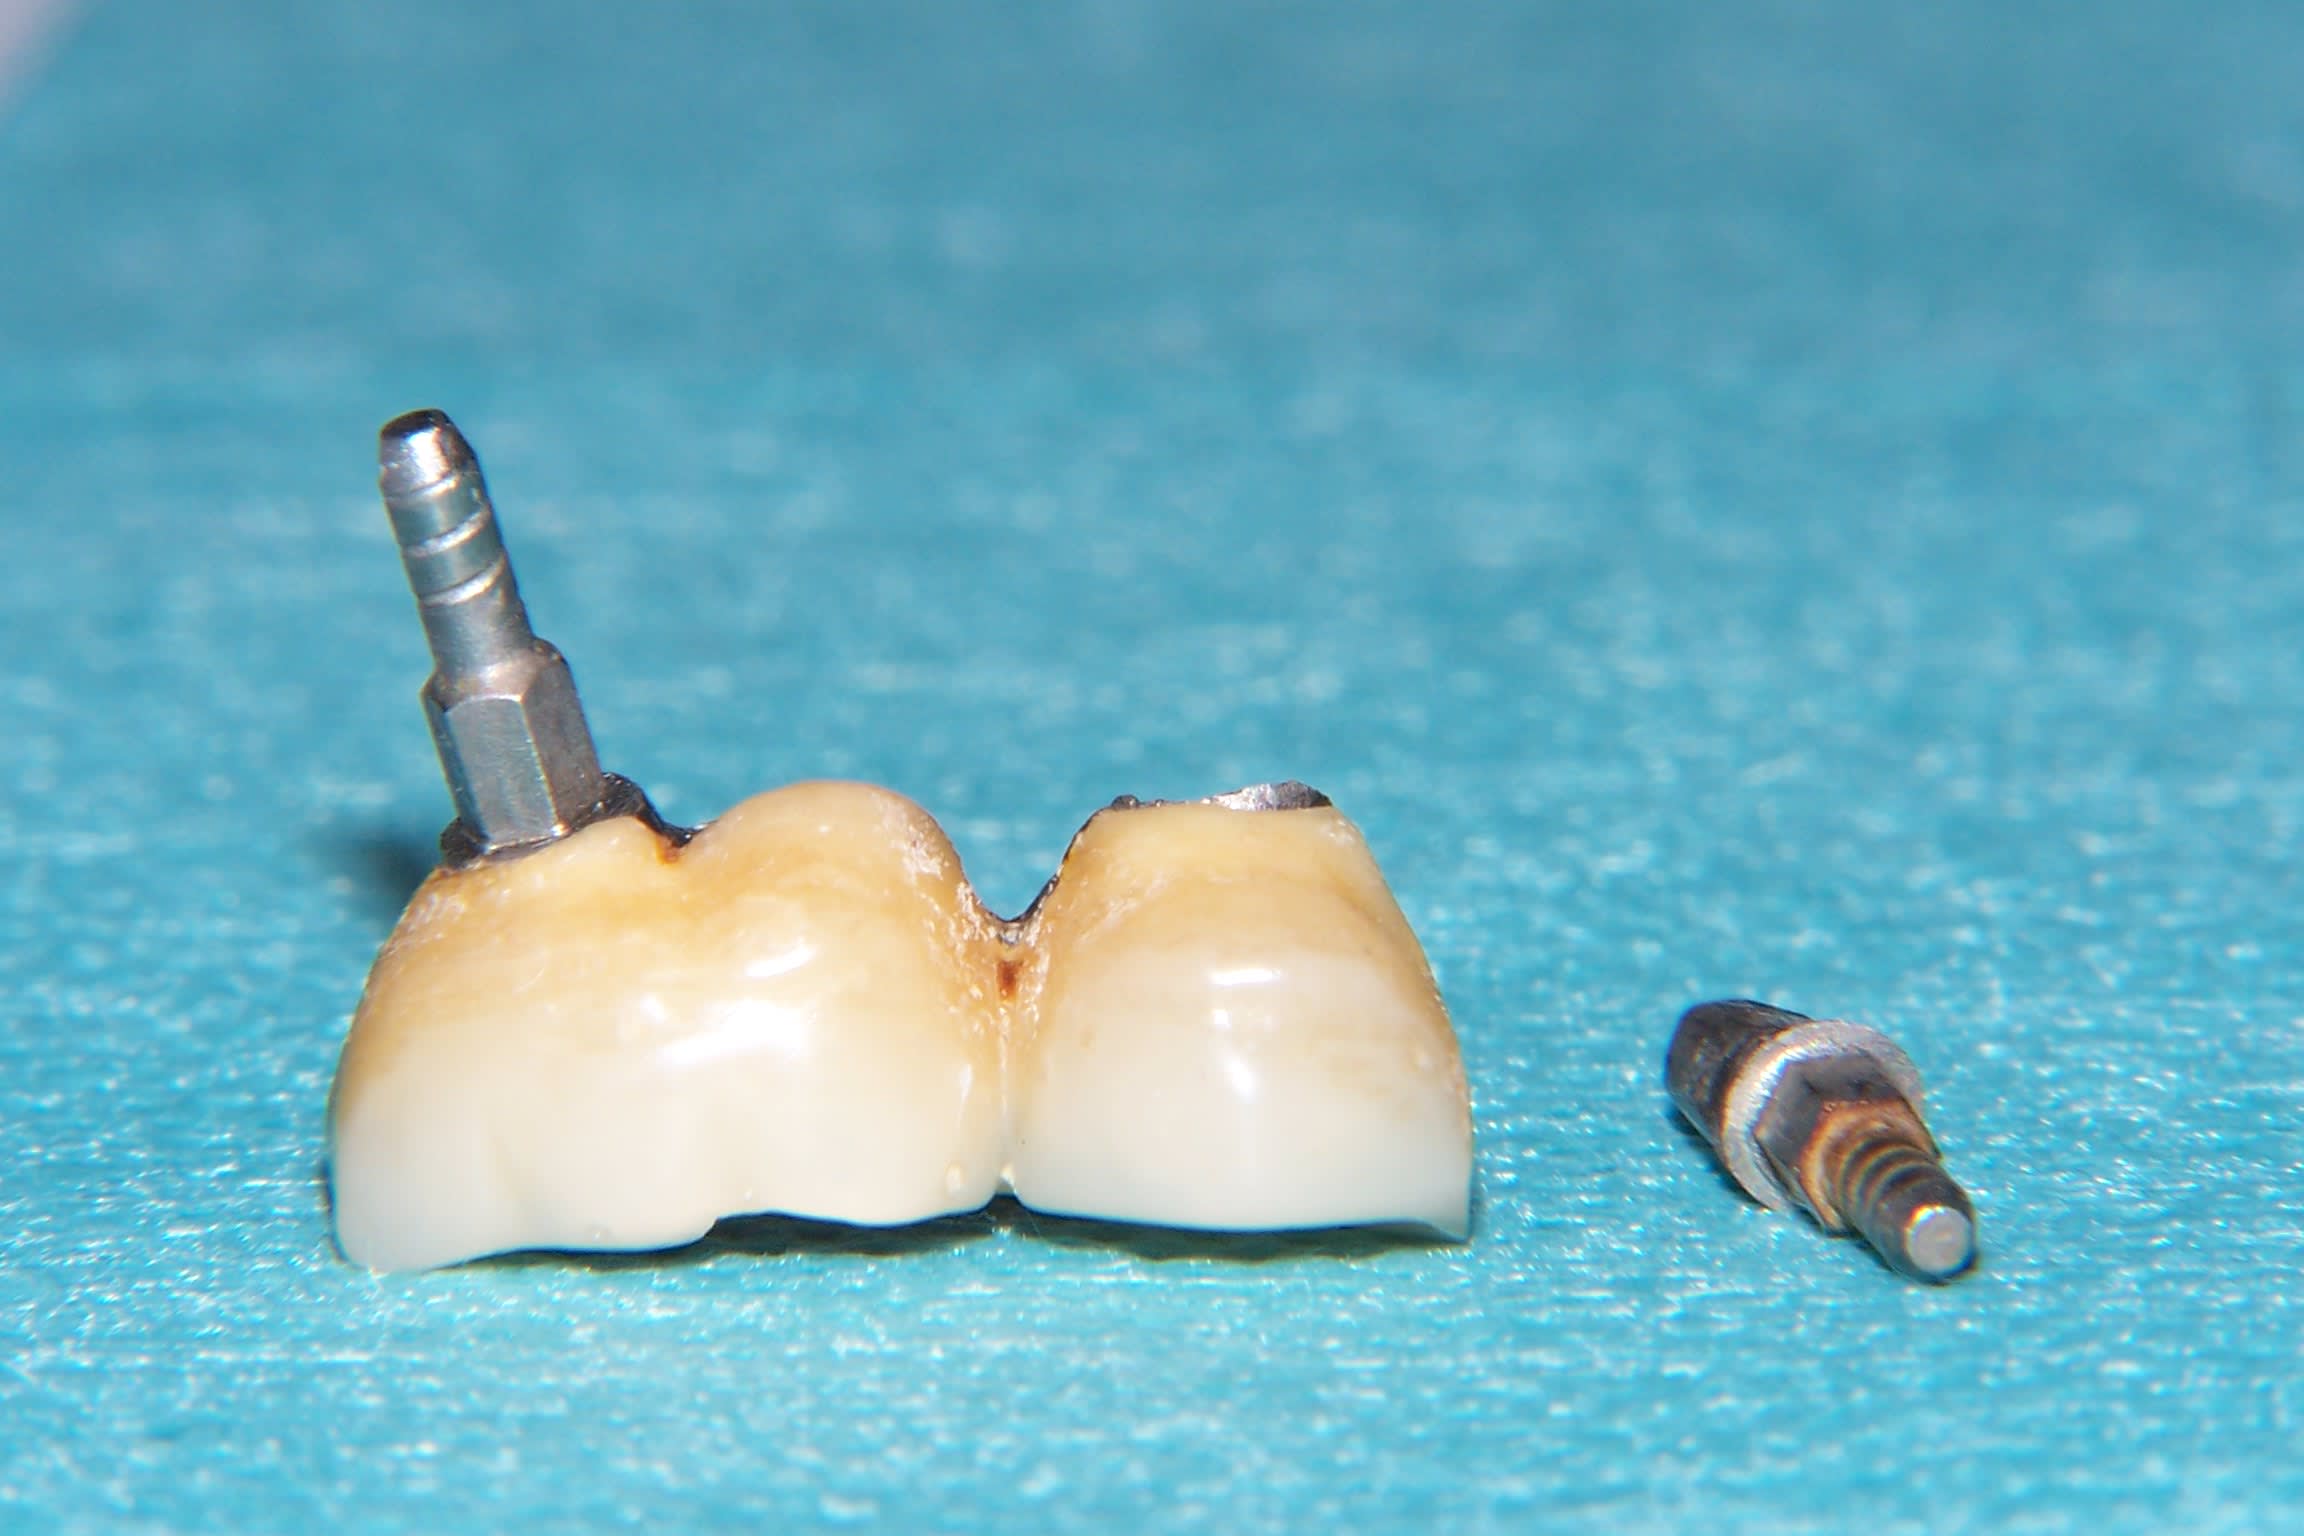

J'ai reçu en une patiente dont les 2 couronnes sur implants 36 et 37 solidarisées se soulevaient pas mal depuis quelques jours. J'ai un peu tiré dessus et j'ai récupéré, les deux CR avec un pilier dans la 37, et le pilier de la 36 est venu à part. Les piliers ne sont pas transvissés mais à priori impactés ( et peut-être scellés ?) directement dans l'implant. Le problème c'est évidemment qu'une fois sorti impossible de remettre les piliers en place. J'ai pas osé forcer...Peut-être qu'il faut un outil spécial ? Sinon les implants sont parfaitement ostéointégrés.

Il s'agit d'un travail fait en Italie, il y a une dizaine d'années. Les implants sont des AZ. La patiente m'a montré deux petites cartes qui lui avait été remises à l'époque (cf photos)

Ca doit être ça, le confrère italien avait ecrit derrière une des cartes, quelque chose comme :" les piliers sont scellés au ciment provisoire dans les implants , et les couronnes au ciment definitif sur les piliers".

Et voilà la fin de l'histoire. Après avoir sorti le pilier de la 37 avec la méthode de fotboy, grand nettoyage des pièces prothétiques. J'avais temporisé avec du Télio Onlay ( Ivoclar) dans le col des implants. Hier lors du RDV, nettoyage des résidus de ciment dans le fut des implants, et franchement heureusement que j'ai encore des tire-nerfs ! petite retouche sur une ou deux faces des hexagones des piliers(pas en titane) car le métal était légèrement déformé et ça rentrait plus. Et rescellement de l'ensemble.